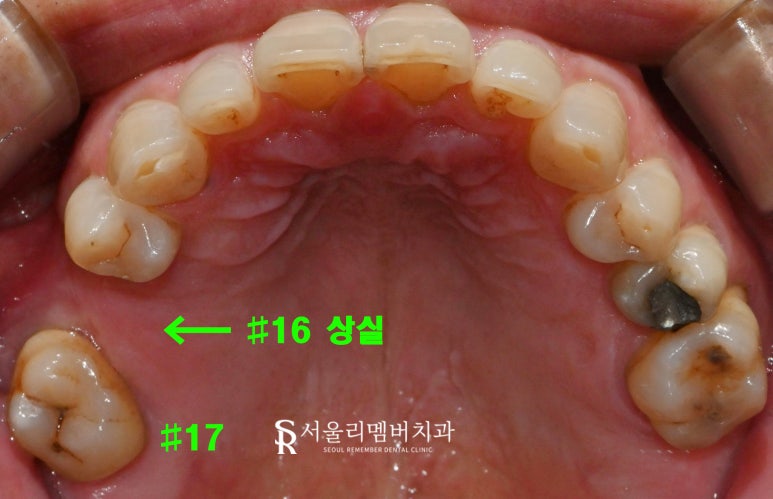

(1) 상악

16번 이가 오래전에 빠지게 되어

치조골이 줄어든 모습이었으며,

17번은 위치가 불안정해져 있었습니다.

(2) 하악

46번이 없는 상태에서 47번은

배열과 위치가 좋지 않았고,

오래된 보철로 인해 기능이 저하된 것이었습니다.

하악 36번도 손실되었으며,

30번대 구치가 전반적으로 부재한 상황이었습니다.